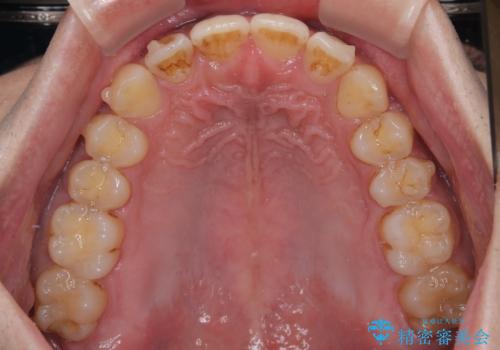

- 上の前歯の正中離開(すきっ歯)と、下顎前歯部の叢生(デコボコ)を主訴に来院された患者様の症例です。

「目立ちにくい装置で治療したい」とのご希望があり、透明のマウスピース矯正であるインビザラインを用いて矯正治療を行いました。

インビザラインは装置が透明で、周囲に気づかれにくいことが大きなメリットです。

取り外しもできるため衛生面でも安心して治療を進めていただけました。